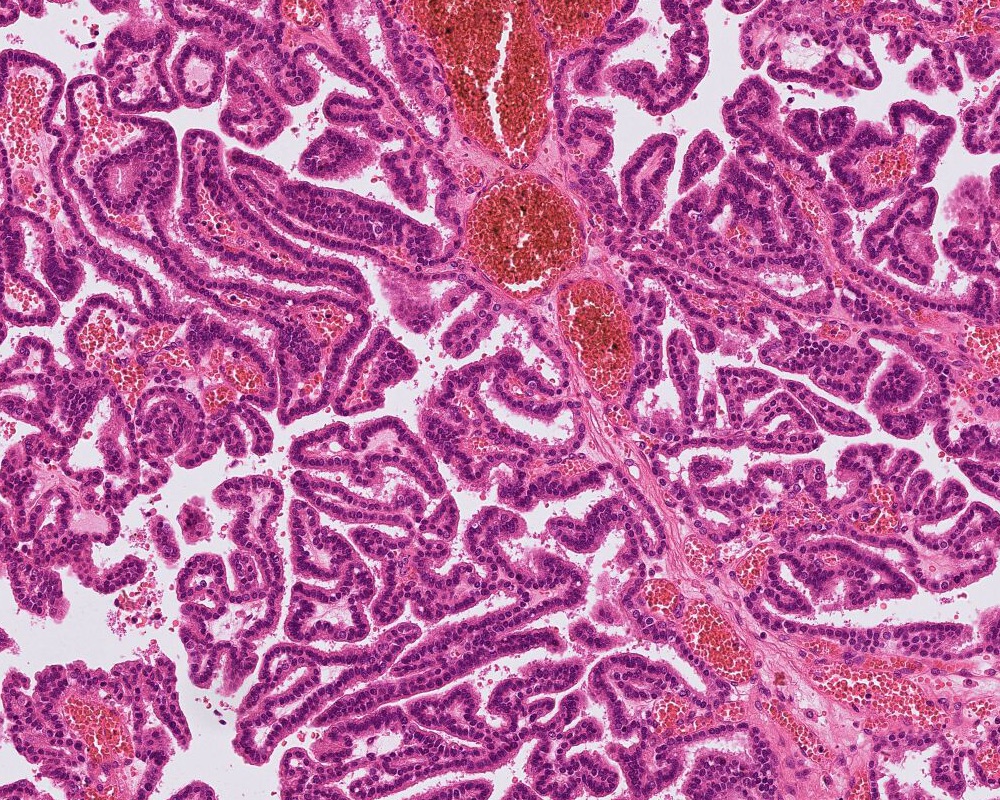

- Atypical choroid plexus papilloma (aCPP, WHO grade 2):

- Higher cellularity relative to CPP

- Moderate nuclear pleomorphism, blurring of papillary pattern

- Occasional mitoses (> 2/10 high power fields), with or without necrosis

Microscopic (histologic) images

A 3 month old boy presented with restless crying and vomiting. His head size was larger than expected for his age. Imaging showed an 8 cm, lobulated, enhancing lesion in the right lateral ventricle. Histology is as above. Which of the following is true?

B. Recent studies suggest 3 distinct molecular entities based on methylation profiling, patient age and tumor location. An atypical choroid plexus tumor is shown in the image.

Choroid plexus tumors are rare intracranial tumors arising in the choroid plexus epithelium of the ventricles. They are more common in children. Histologically, they are classified into 3 categories: choroid plexus papilloma (CPP, WHO grade 1), atypical choroid plexus papilloma (aCPP, WHO grade 2) and choroid plexus carcinoma (CPC, WHO grade 3). Although any of these tumors can have CSF spread and recur following treatment, the latter is associated with poor outcome and higher recurrence rate. Recent studies have shown that CPP and aCPP are genetically similar but CPP and aCPP are genetically distinct from CPC. The CPCs are mostly driven by loss of function or mutations of tumor suppressor gene TP53 and may be associated germ line mutations (Li-Fraumeni syndrome). Furthermore, based on methylation profiling, tumor location and age, 3 distinct subgroups with prognostic significance have been described. The advances in understanding of genetics may help deliver appropriate personalized treatment.